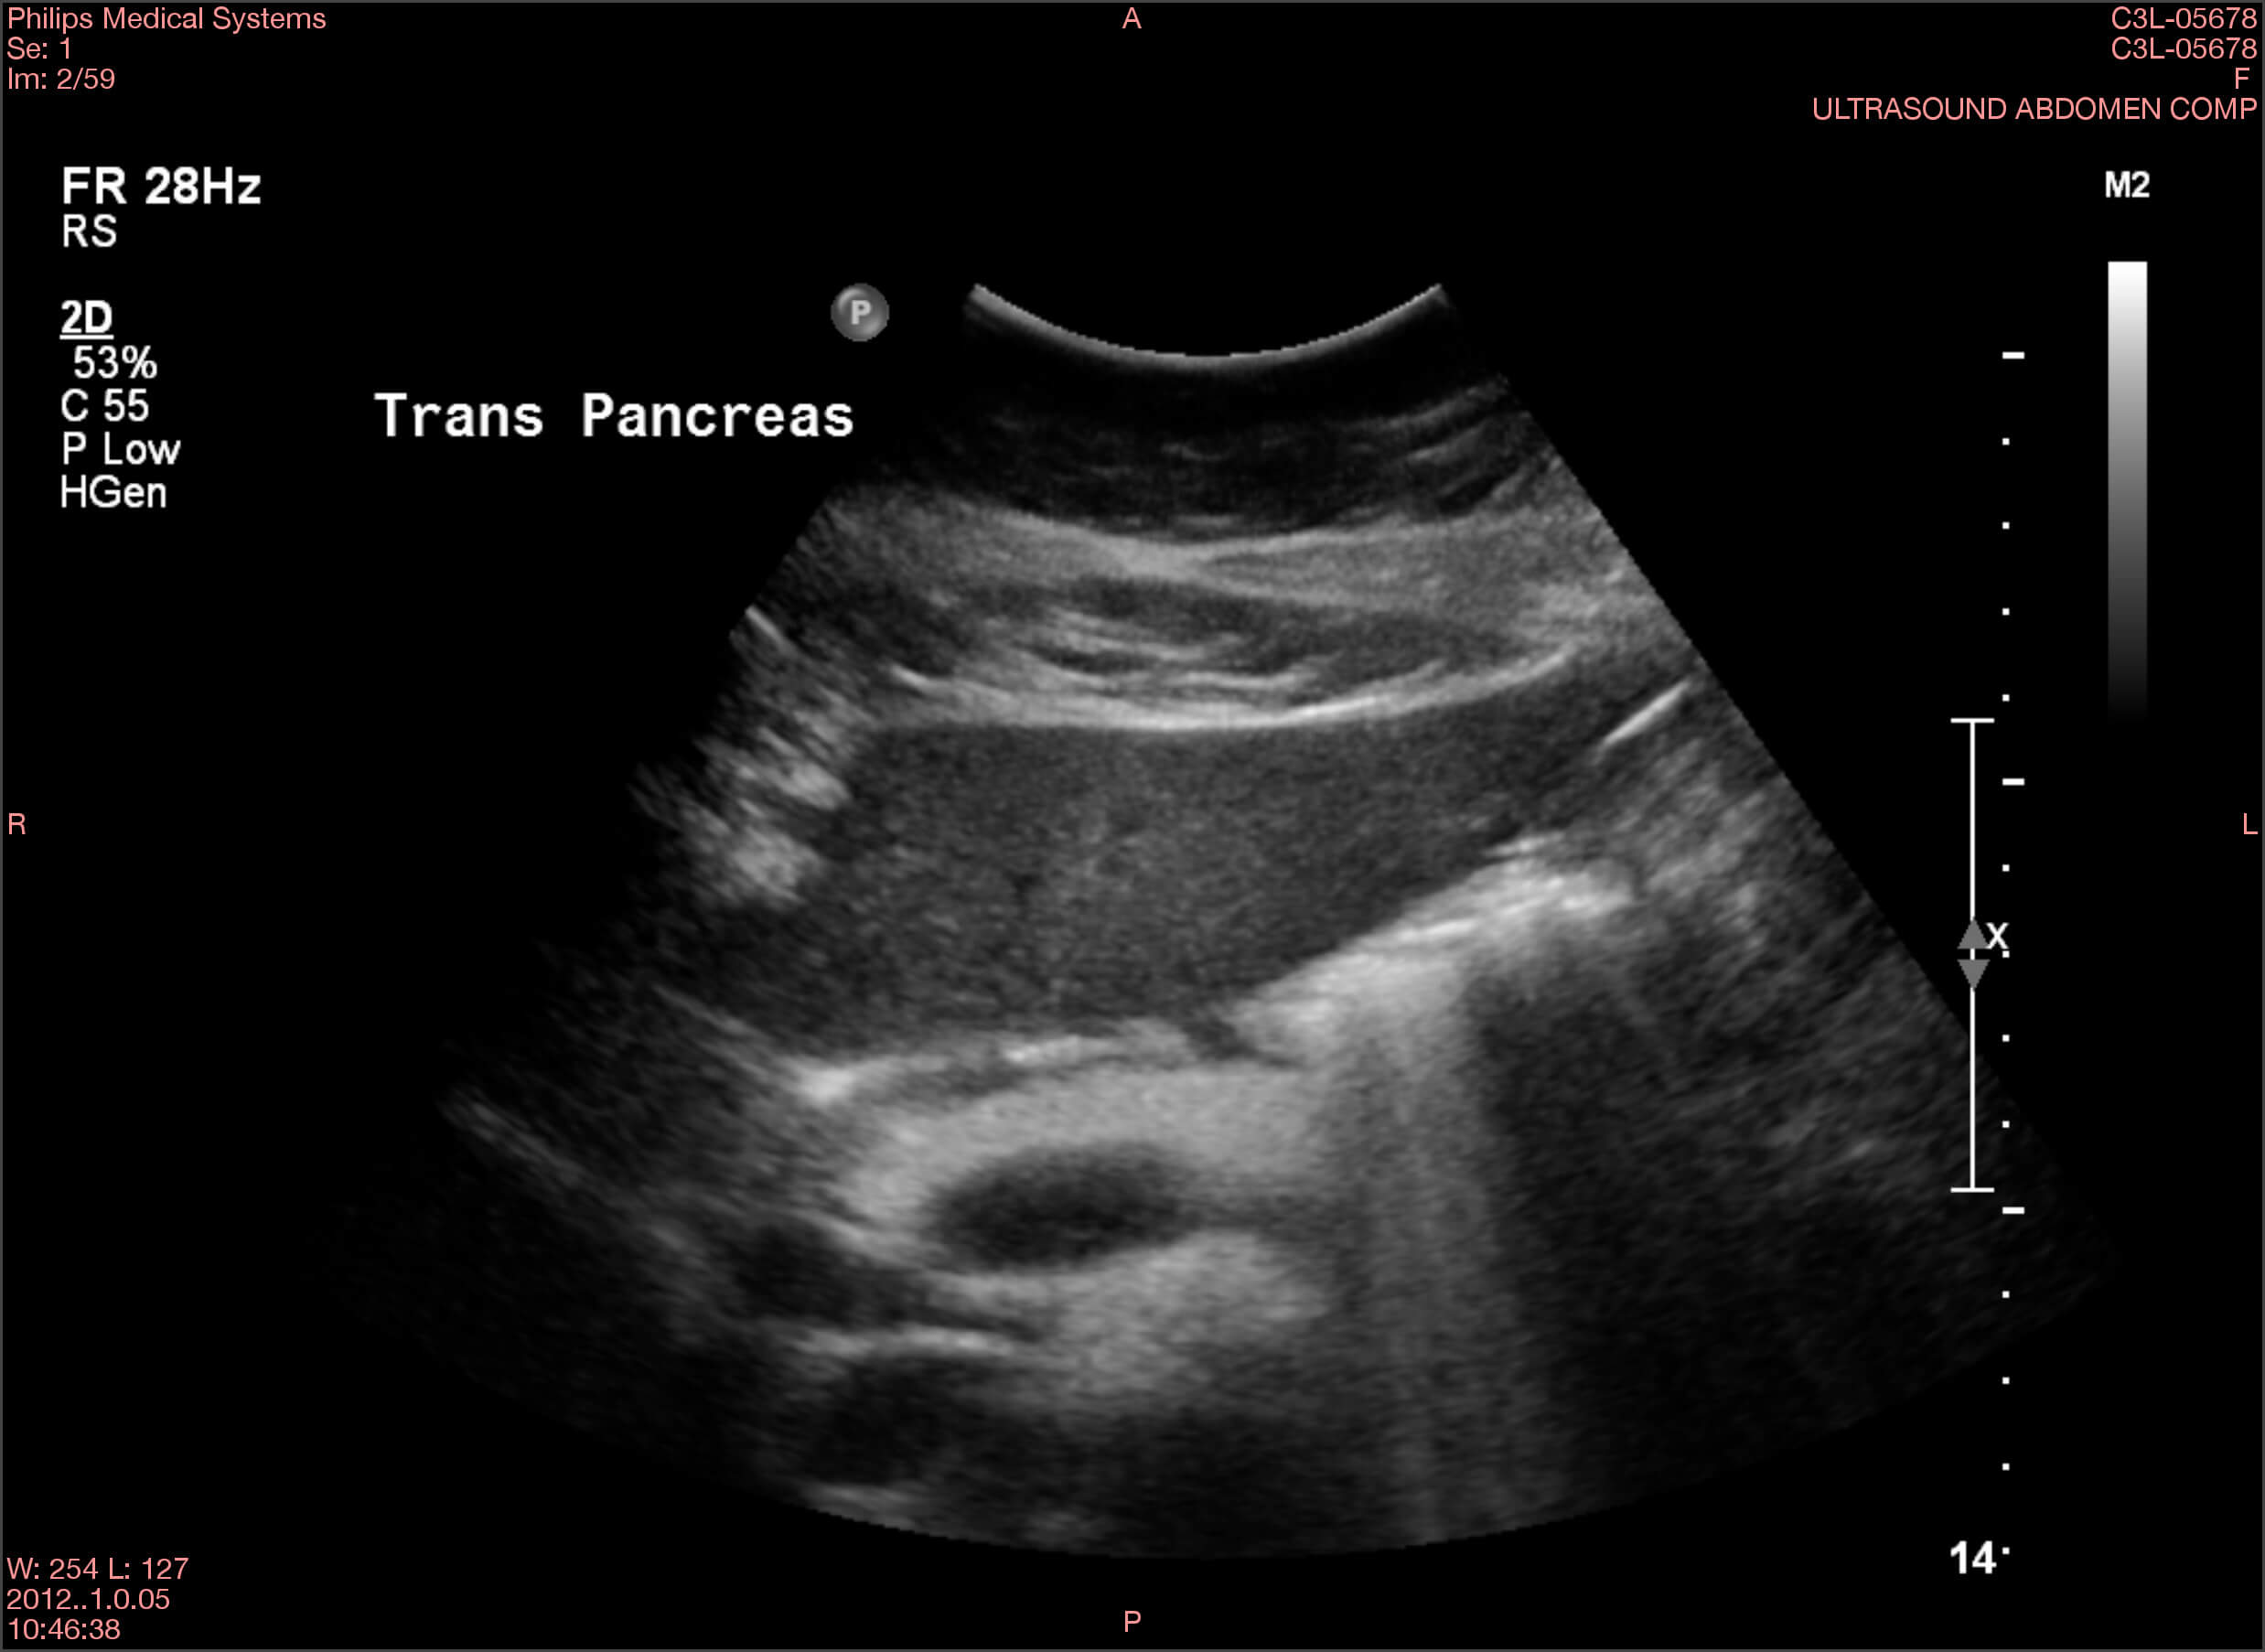

Die Ergebnisse der durchgeführten Untersuchungen kannst du dir hier anschauen:

Die Befunde geben eindeutige Hinweise auf die Erkrankung von Frau Lorenz. Wie bewertest du die Ergebnisse?